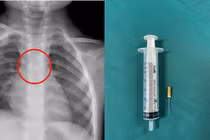

Bệnh nhi 3 tuổi gặp nguy hiểm do dị vật kim chọc tủy trong khí quản, các bác sĩ đã nội soi lấy ra thành công.